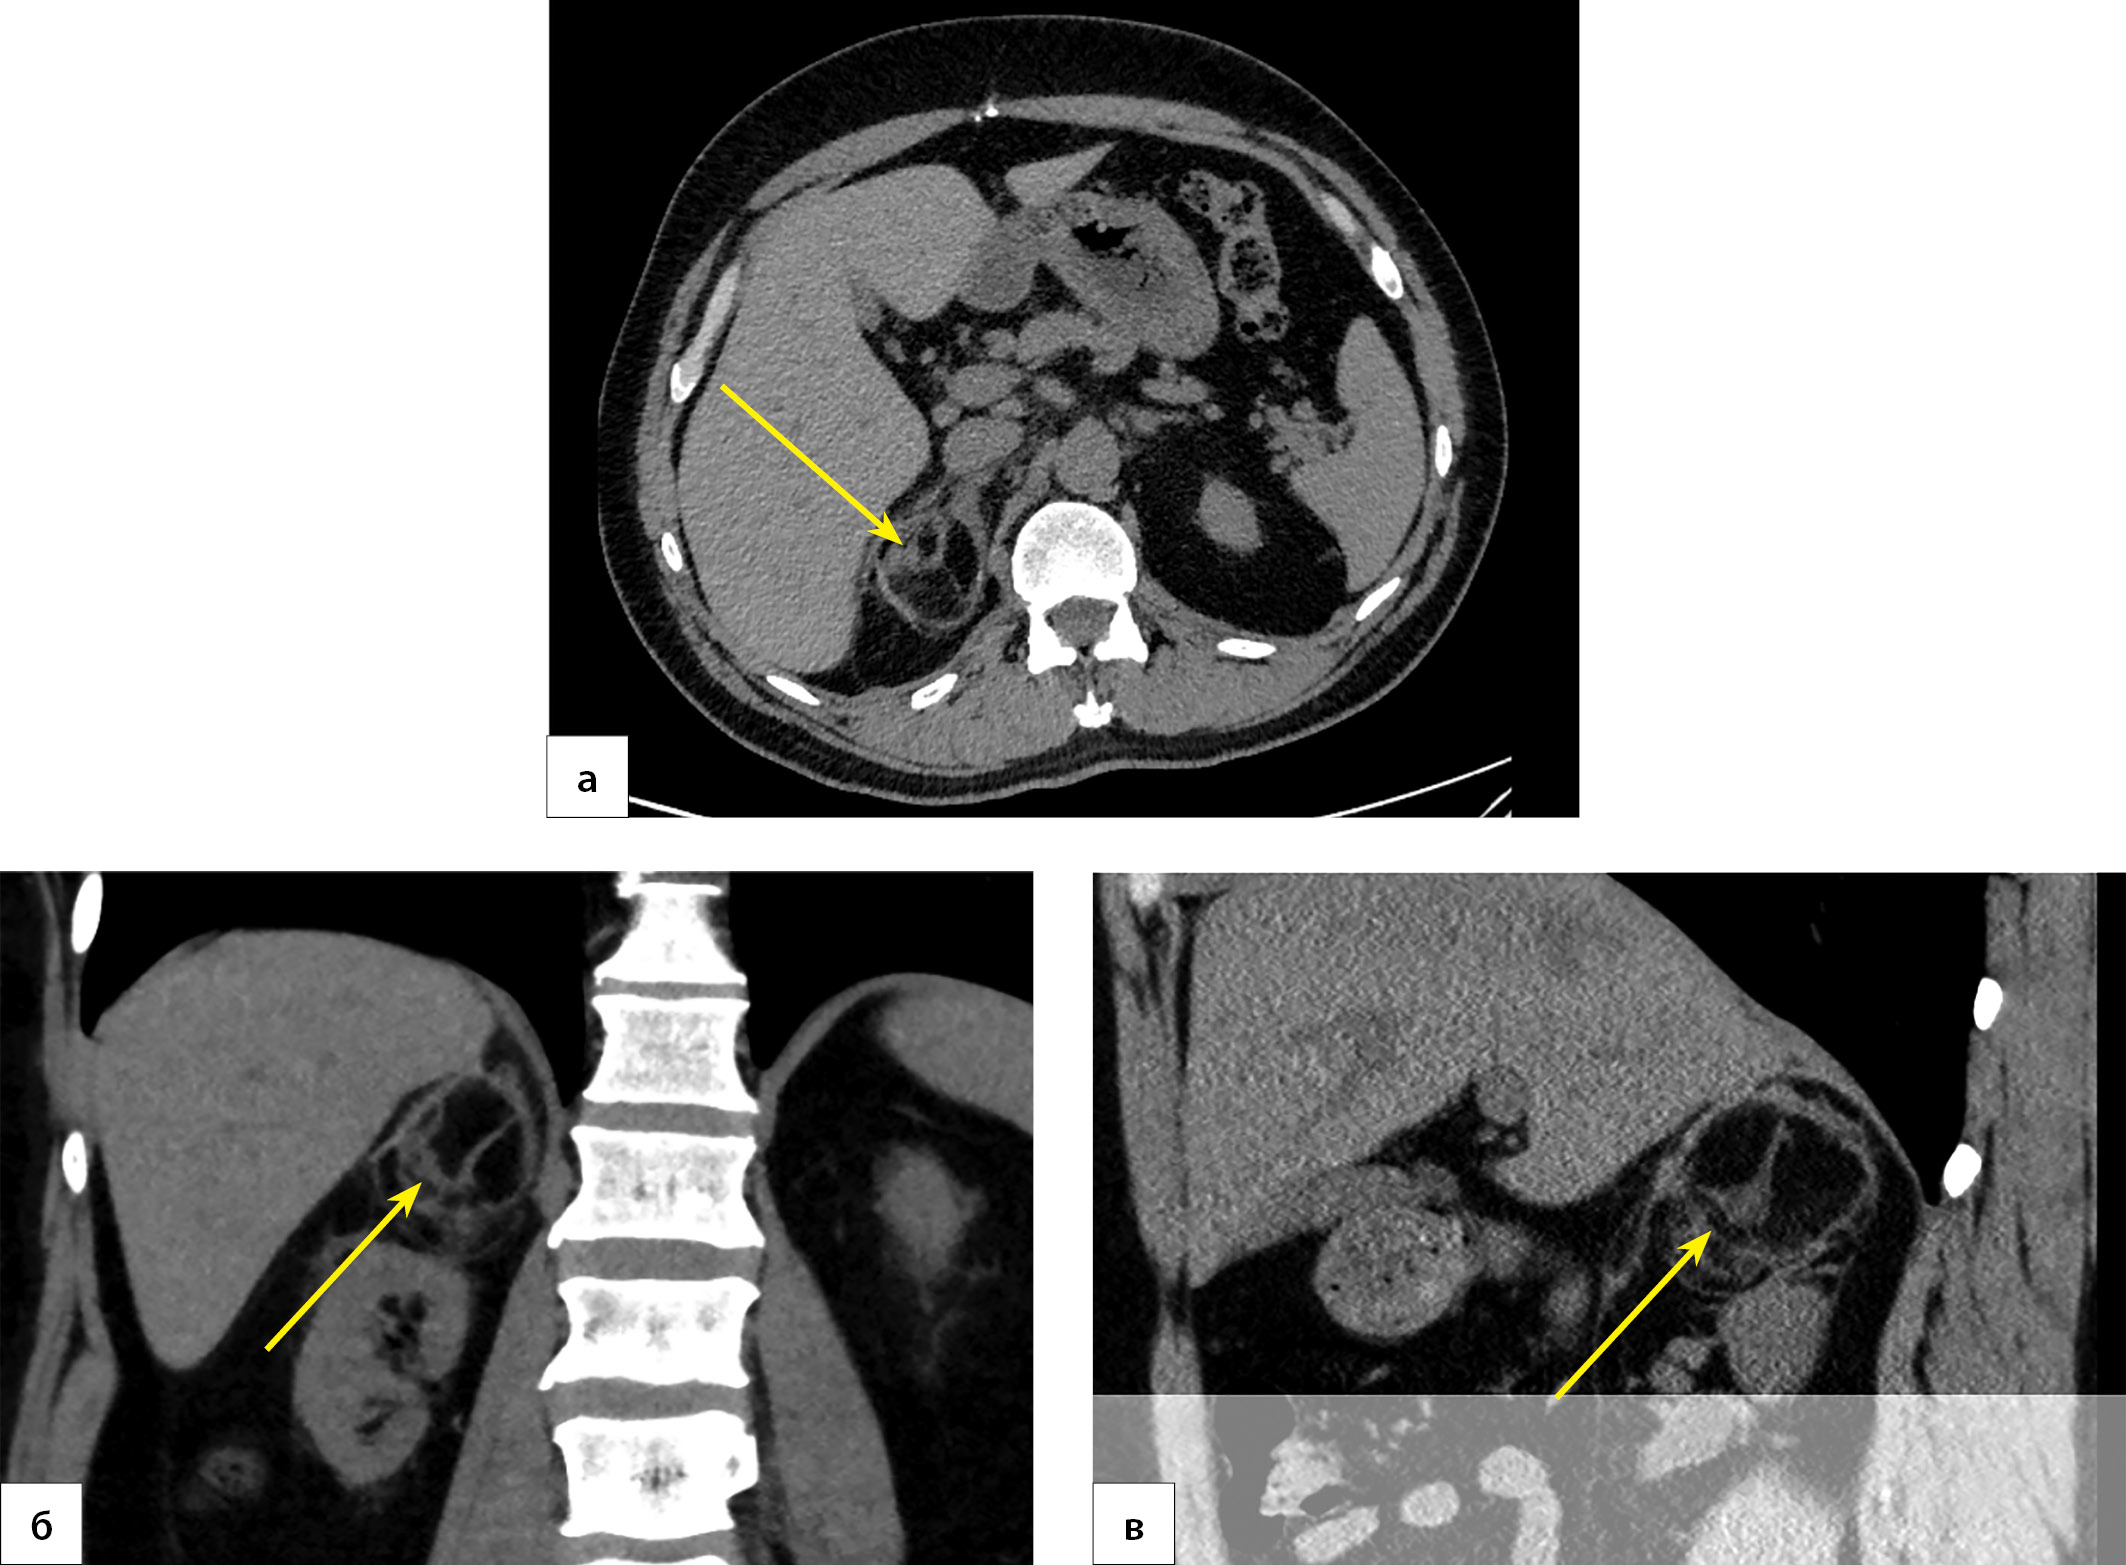

6. Рисунок 6. Пациент П., 45 лет. МСКТ брюшной полости. Организация гематомы (маркирована стрелкой): а) корональная проекция; б) аксиальная проекция; в) сагиттальная проекция. | |